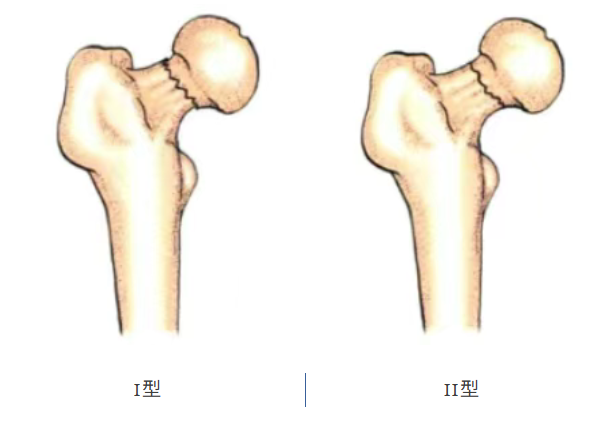

根据骨折的移位程度进行分类:Garden分型(最常用临床分型)

I型、II型,因为骨折断端无移位,骨折损伤程度较小,属于稳定型骨折。

III型、IV型,因骨折断端移位明显,骨折损伤较大,属于不稳定型骨折。